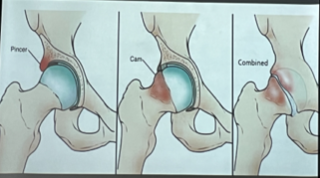

Tipos

PINCER: Coxa profunda. Pico que alarga la cavidad acetabular. Común en mujeres:

CAM: Deformidad cabeza femoral. Común hombres

MIXTO